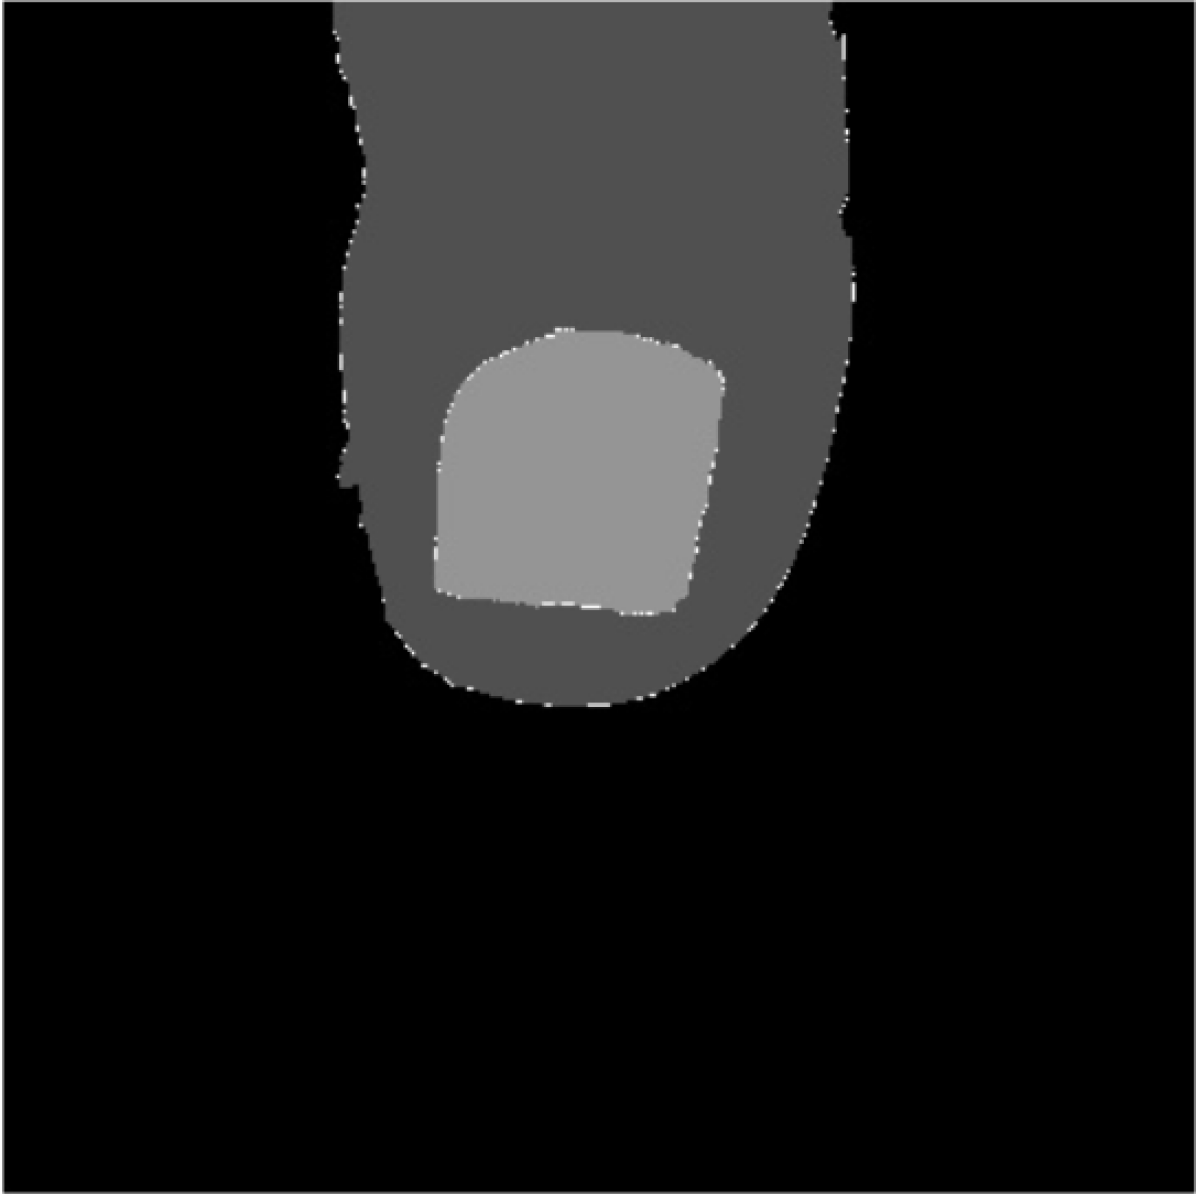

In Fig. 7(a), we can appreciate that the contours of the nail are sharp. Thus, provided the initial markers are corrected, the growth of the nail and skin regions would be prone to stop at these edges. This has been actually the case when processing images in practice, as shown in Fig. 7(d).

Several performance metrics are used to quantify the results obtained. They complement the visual representations, such as the one in Fig. 7, since they exhibit the results over the whole dataset. Since we are dealing with a segmentation task, we employ pixel-wise measures. The performance measures used are sensitivity, specifity, accuracy, precision, F-measure and Cohen’s kappa. They complement each other: each of them captures distinctly different deviations from the expected result.

Table 3 presents the results obtained by evaluating the final mask—provided by the watershed algorithm—against a manually built ground truth. The results are evaluated according to different metrics. We remark the role of the -measure, the harmonic average of precision and recall; and the Cohen’s , which indicates the rate of agreement between the two classes. We consider both of them as being high, in particular when compared to other segmentation tasks.